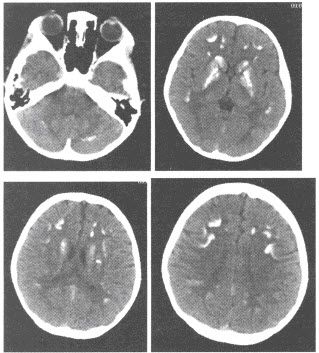

(单选题)该患者的CT所示,结合病史,该患者最可能的诊断是()

A:肺脓肿

B:肺癌

C:炎性假瘤

D:肺结核

E:转移瘤

F:大叶性肺炎

(单选题)本病最可能的病理类型为()

A:腺癌

B:小细胞癌

C:大细胞癌

D:鳞癌

E:鳞腺癌

F:以上都不是